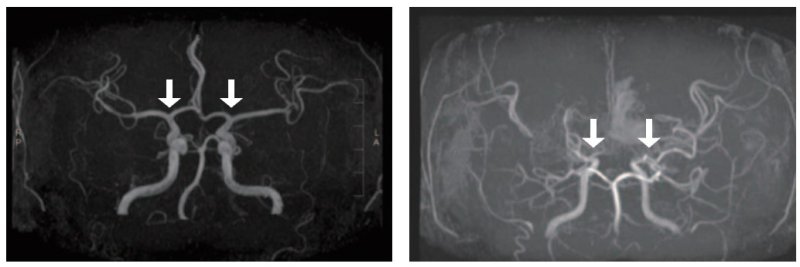

[서울=뉴시스] 사진 왼쪽부터 정상 및 모야모야병 환자의 뇌혈관. (사진= 서울대병원 제공)

모야모야병은 뇌로 혈액을 공급하는 혈관이 원인 없이 점차 좁아지는 만성 진행성 뇌혈관질환이다. 10세 전후 소아와 40세 전후 성인에서 주로 발병하며, 부작용으로는 뇌혈관이 막히거나 파열되는 허혈성·출혈성 뇌졸중이 있다.